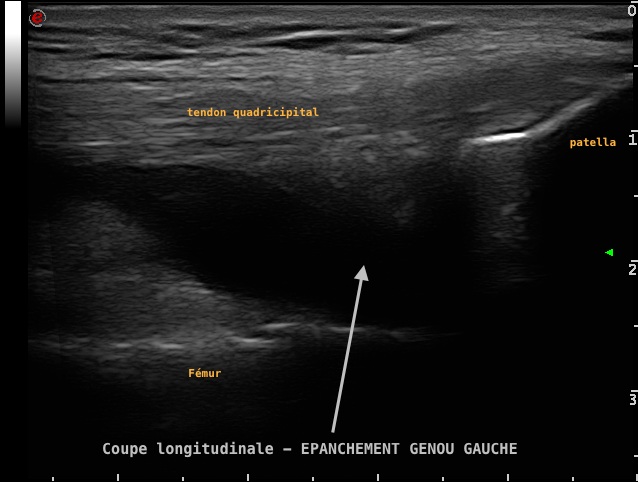

Epanchement intra-articulaire du genou, visible en échographie, dans le cadre d'une arthrite